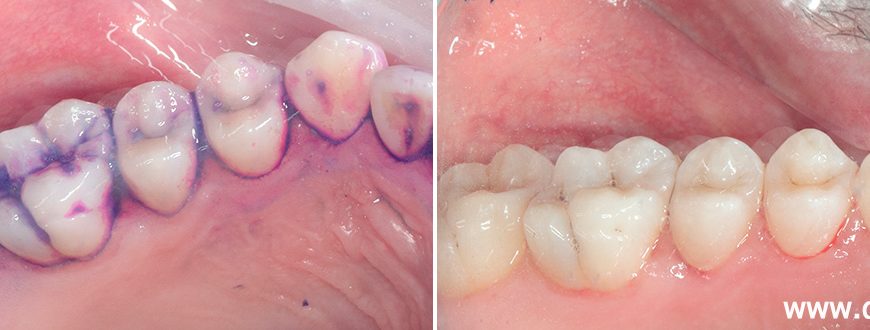

Профессиональная гигиена полости рта – это комплекс процедур, проводимых стоматологом-гигиенистом, направленных на удаление зубного камня, налета и пигментированного налета с поверхности зубов и из пародонтальных карманов. Эти процедуры являются неотъемлемой частью профилактики пародонтита и позволяют значительно снизить риск его развития или прогрессирования.

Ключевым элементом профессиональной гигиены является ультразвуковая чистка зубов. Ультразвуковой скалер эффективно удаляет твердые отложения – зубной камень – из труднодоступных мест, где обычная зубная щетка не справляется. После ультразвуковой чистки проводится полировка поверхности зубов специальными пастами, что делает их гладкими и препятствует повторному накоплению налета.